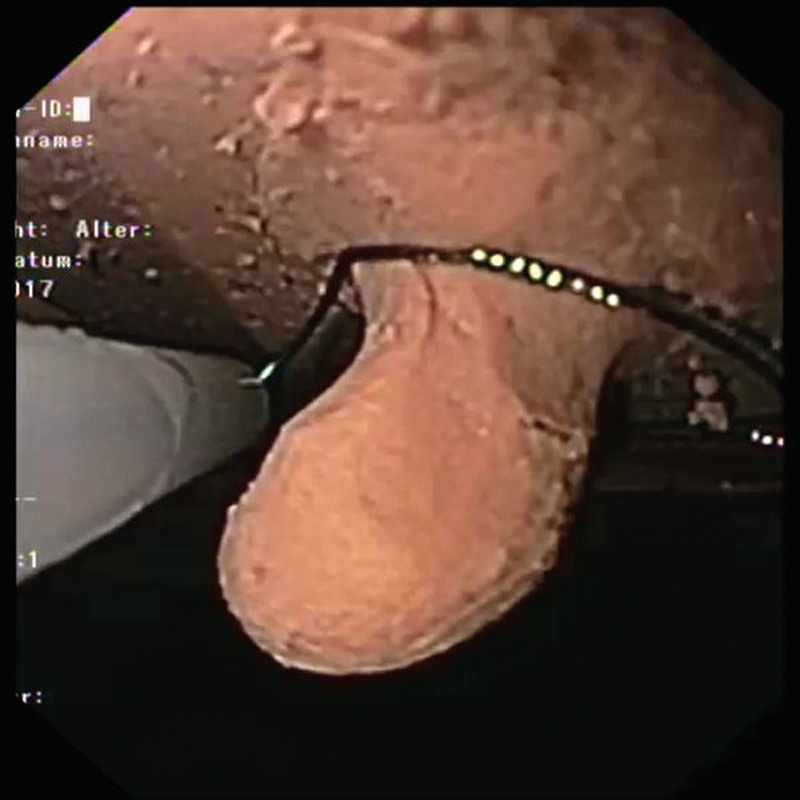

Simulator Gastro združuje možnosti realističnega anatomskega modela in usposabljanja za intervencijsko endoskopijo. Veliko število različnih vložkov omogoča zdravljenje polipov, kot so vbrizgavanje, dvigovanje, rezanje in odstranjevanje, simulacija zaustavitve krvavitve, stentiranje in drugo. Simulator in vložki so izdelani iz popolnoma umetnega materiala.

- Odstranjevanje tkiva s hladno zanko, npr. polipektomija

- Varikacijska ligatura

- Zdravljenje krvavitev / zaustavljanje krvavitev z injekcijami, sponkami in ligiranjem traku